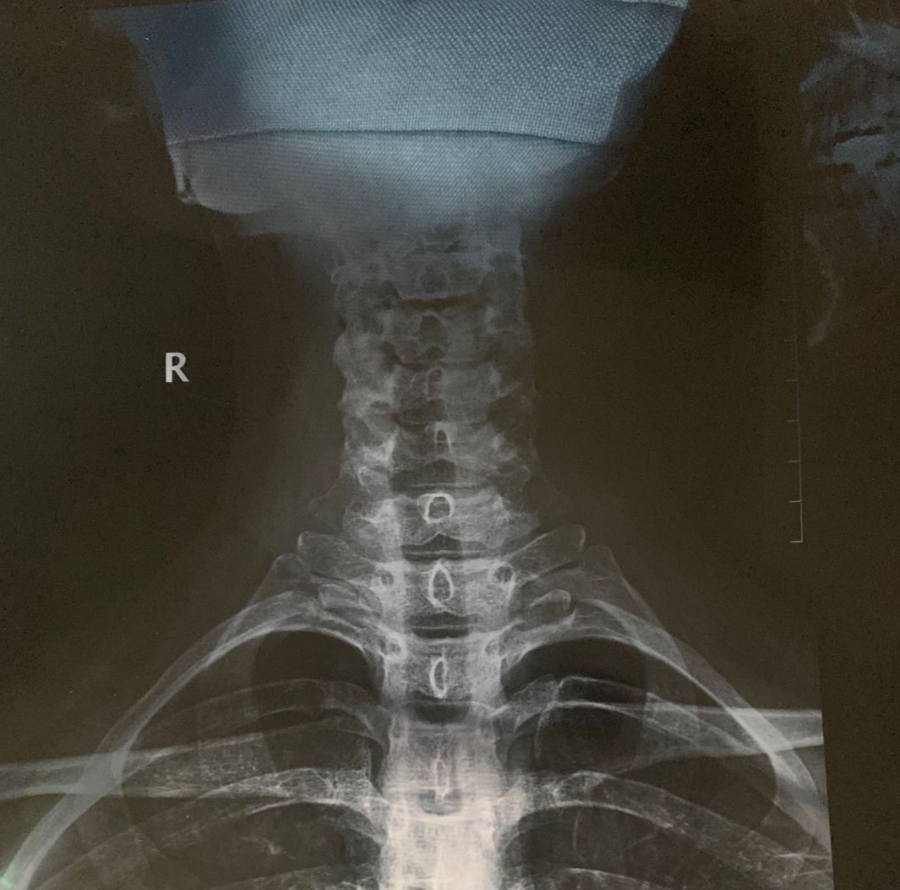

我们还是来说说人体三角区吧!这些区域是人体最脆弱的地方,守住它们,就关上了疾病的大门!颈部金三角区是指颈后枕骨以下包括第一颈椎和第二颈椎。之所以被称之为黄金三角区,是因为这个区域两侧有很多的血管神经通过。但是如果长期坐姿不良或者睡觉喜欢枕比较硬、比较高的枕头,会使颈部肌肉酸痛甚至使颈椎的生理弯曲消失,颈椎变直,压迫周围的血管神经,从而导致一些颈椎病的轻微症状,比如头痛、头晕、恶心等。1. 常前、后、左、右活动脖子,同一个姿势维持1小时左右,要做些头和上肢的前屈后伸、旋转运动等。